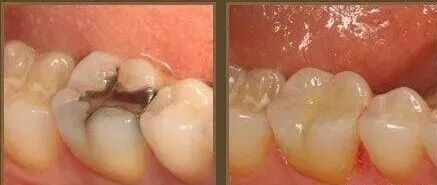

第一階段:牙齒咬合面有黑線,大牙一般最常見,說明開始蛀牙了,牙釉質被細菌齲壞,但不痛不癢,會出現窩溝齲得及時補牙,而不是去洗牙;

第二階段:牙齒出現小黑洞,說明引起中度蛀牙,細菌腐蝕來到牙本質,伴隨著牙齒敏感,黑色腐敗物質其實就是細菌的産物,這時候還可以再補牙;

複合樹脂,接近牙齒顔色的填充材料,粘接性還不錯,特別耐磨抗腐蝕,關鍵補牙後還看不出有補過痕迹,大人和小朋友都可以使用。